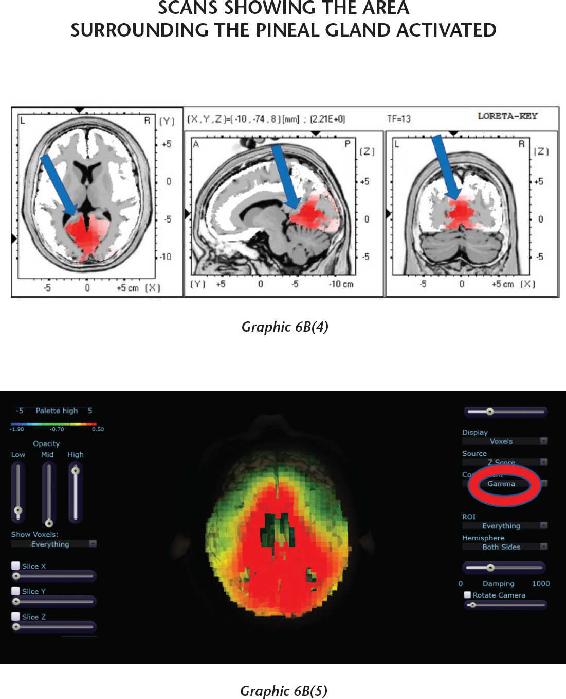

Once you are beyond your associations to this material world and you are in the unified field—chock-full of infinite possibilities—biological systems exist for taking that energy that’s beyond the vibration of matter and turning it into imagery in the brain. That’s where the pineal gland comes in, the subject of Chapter 12. Think of your pineal gland—a tiny gland perched in the central back area of your brain—as an antenna that can transduce frequencies and information and turn them into vivid imagery. When you activate your pineal gland, you are going to have a full-on sensory experience without your senses. That internal event will be more real to you in your mind while your eyes were closed than any past external experience you’ve ever had. In other words, in order to lose yourself fully in the inward experience, it has to be so real that you are there. When this happens, this little gland transmutes melatonin into some very powerful metabolites that cause you to have that type of experience. We will study the properties of this gland and then you will learn how to activate it.